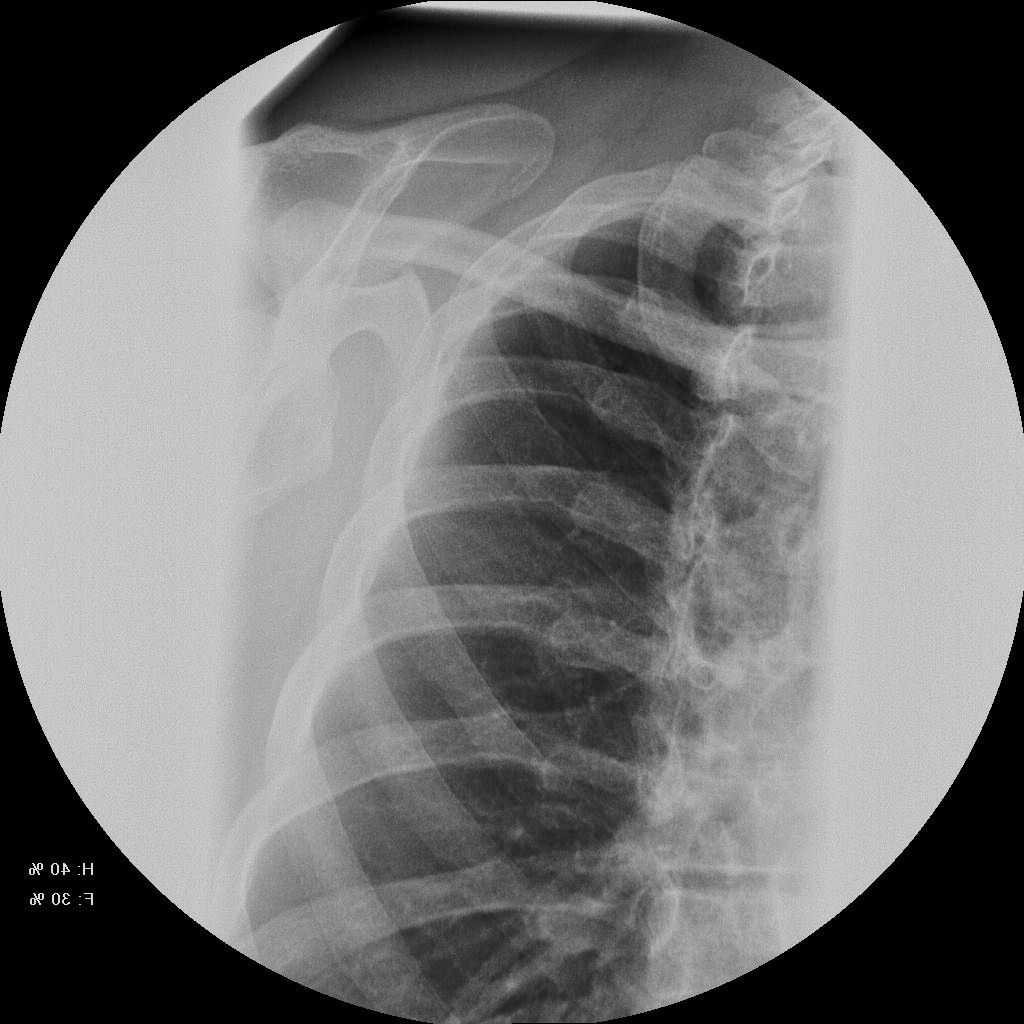

Медицина и диагностика: Аномалии ребер на рентгене